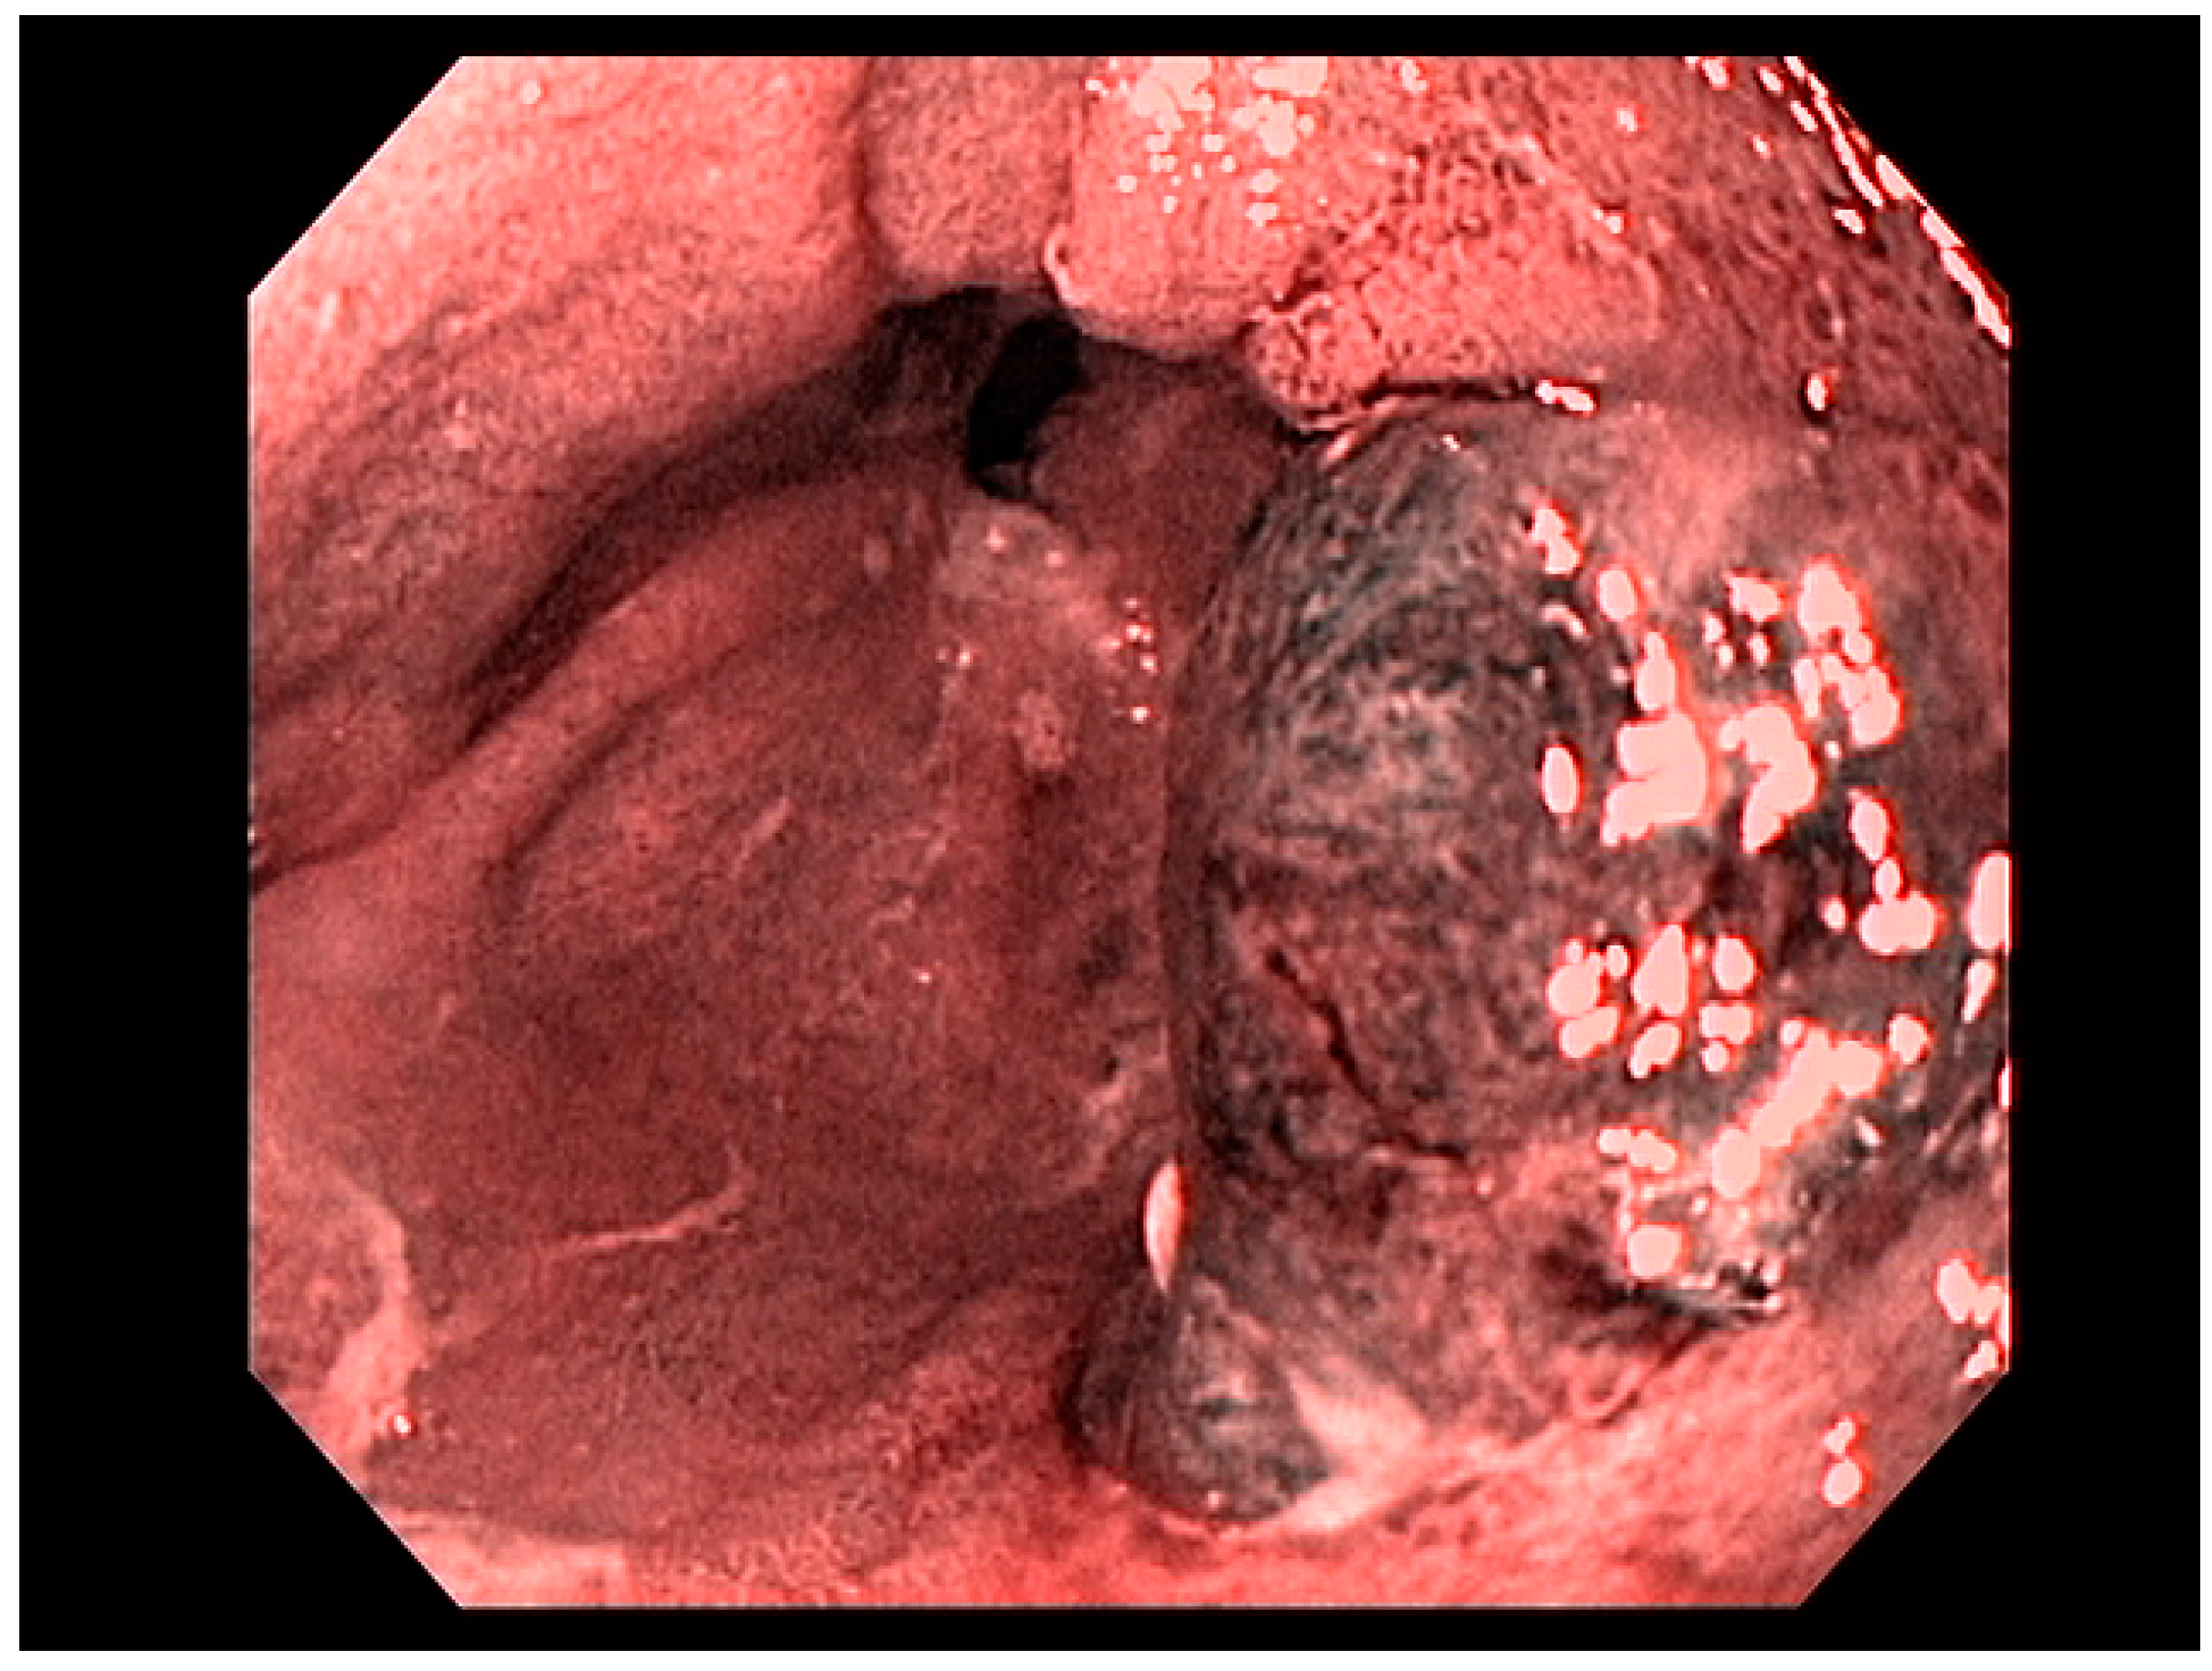

4.2. Early Gastric Cancer (EGC)

4.3. Endoscopic Ultrasound in Staging of Gastric Cancer

- Waddingham, W.; Nieuwenburg, S.A.V.; Carlson, S.; Rodriguez-Justo, M.; Spaander, M.; Kuipers, E.J.; Jansen, M.; Graham, D.G.; Banks, M. Recent advances in the detection and management of early gastric cancer and its precursors. Front. Gastroenterol. 2020. [Google Scholar] [CrossRef]